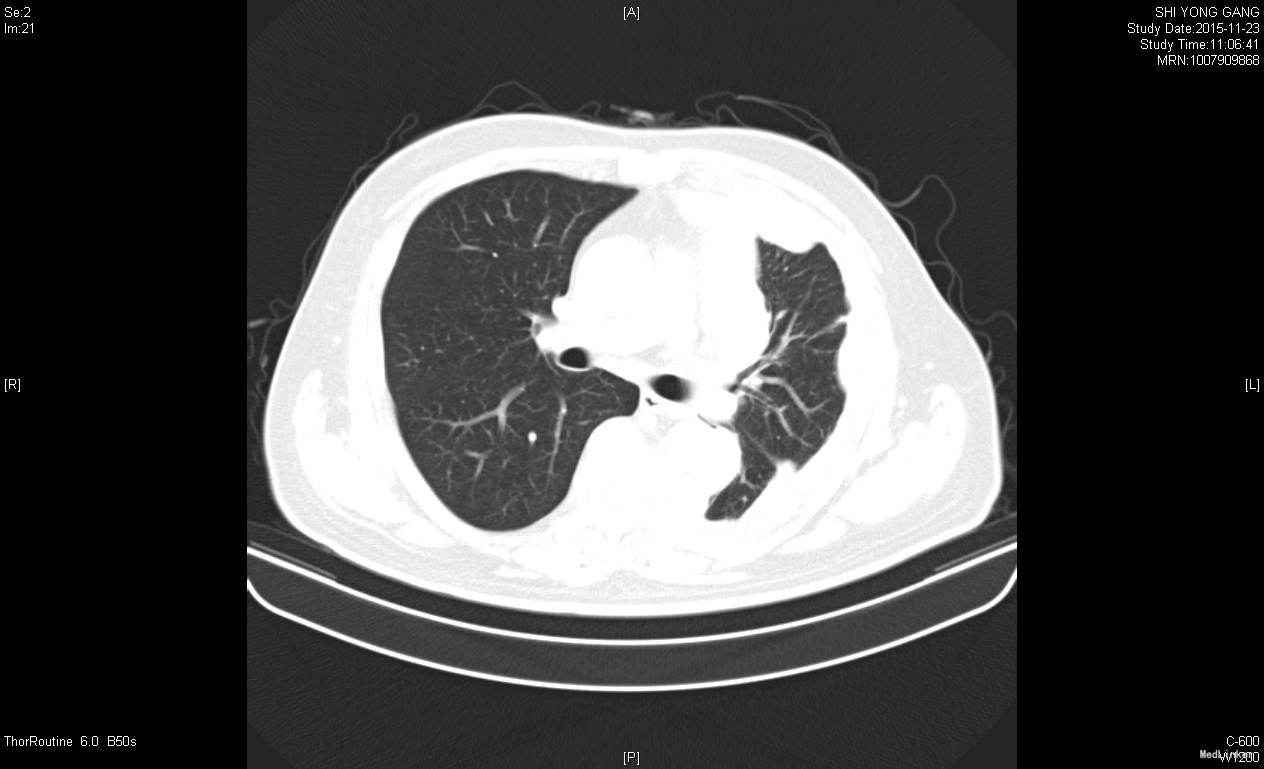

诊断胸膜恶性间皮瘤。治疗力比泰+顺铂化疗,症状好转,胸水吸收。

患者治疗6周期后,因经济原因停止化疗。今年复查胸片示右肺大量实变,b超证实非胸水。考虑为肿瘤进展。胸膜间皮瘤往往以胸水为首发,易误诊漏诊,对反复胸水治疗效果欠佳者,应尽早应胸膜活检。胸膜间皮瘤最佳治疗方案是力比泰。